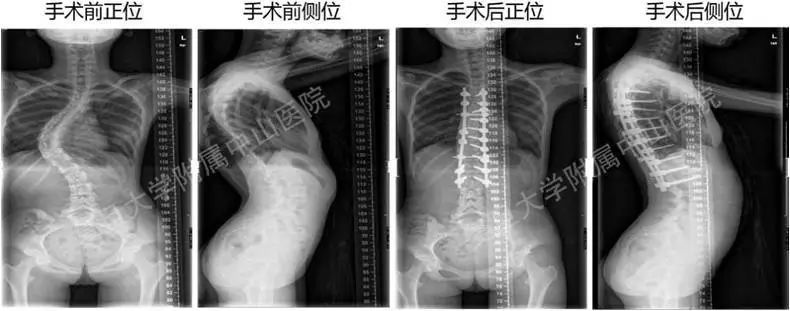

图五 脊柱侧弯的手术治疗

(图片来自复旦大学附属中山医院)

3、手术矫正治疗:仅适用于小部分角度较大(cobb角40°以上)、或者是角度加重较快、保守治疗无效的患者。但是对于先天性脊柱畸形、神经肌肉源性的脊柱畸形,这些患者可能需要脊柱外科医生尽早手术干预,以免出现侧弯相关的心肺功能障碍。前述病例中小李因严重脊柱侧弯(cobb角60°),为避免进行性加重(造成畸形、呼吸或心脏问题),予以手术干预(见图五:小李术前及术后脊柱侧弯矫正情况)。